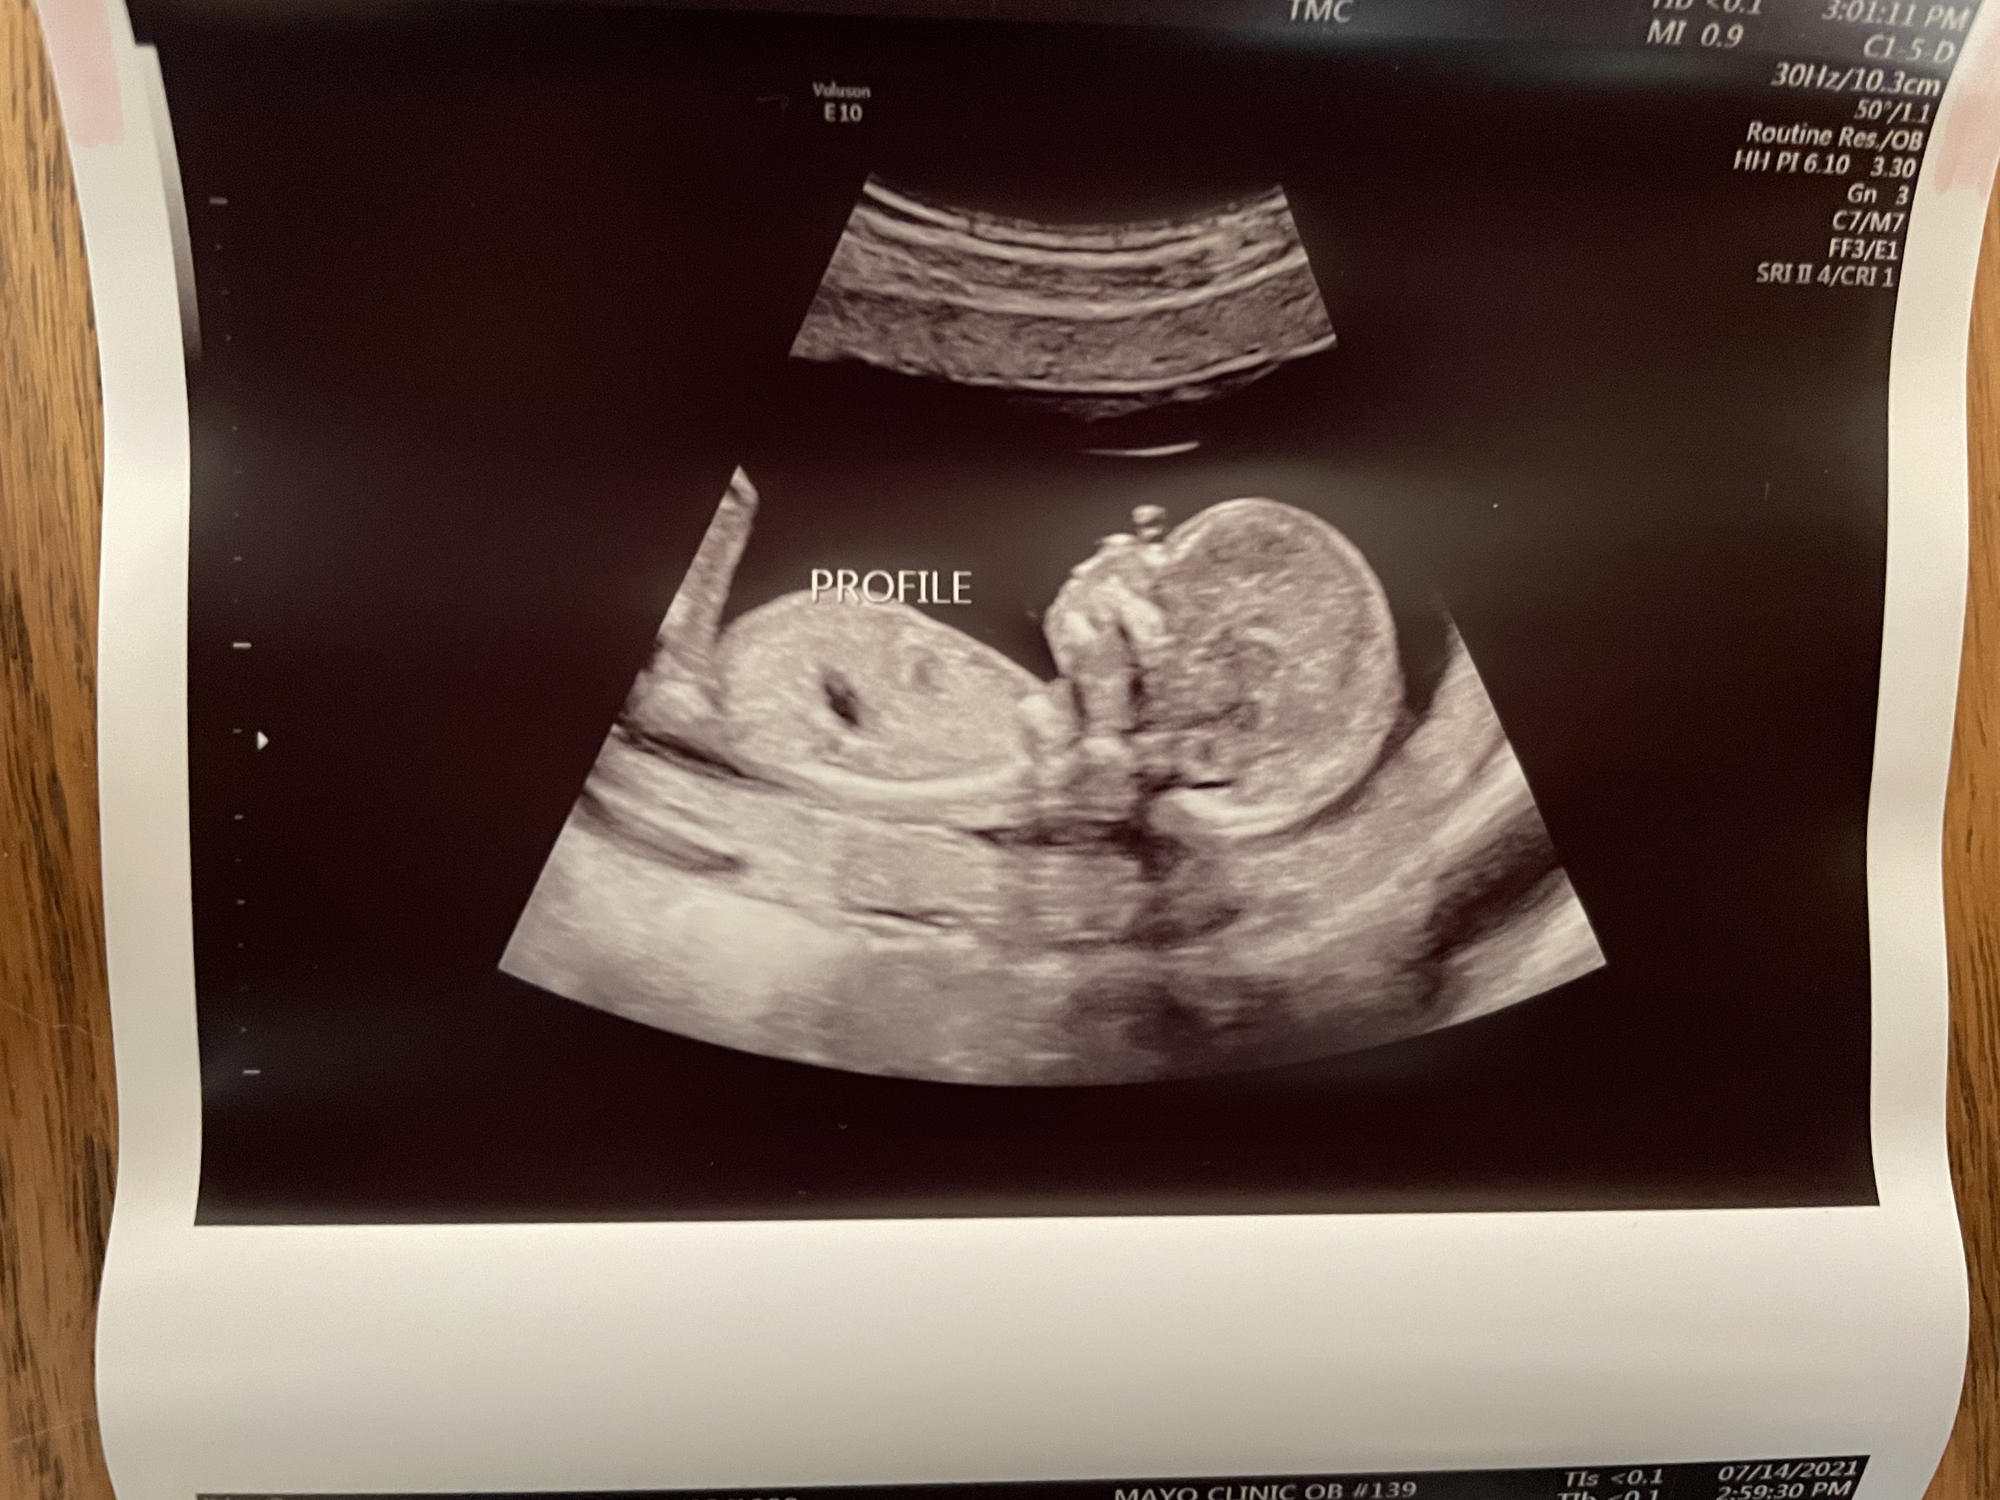

We had our follow up scan today to get the remaining pictures of baby girl's heart - all looks great, thank goodness! She's sucking her thumb here. She was still very active OR curled up in a ball and didn't want to move. Stubborn like her mama.